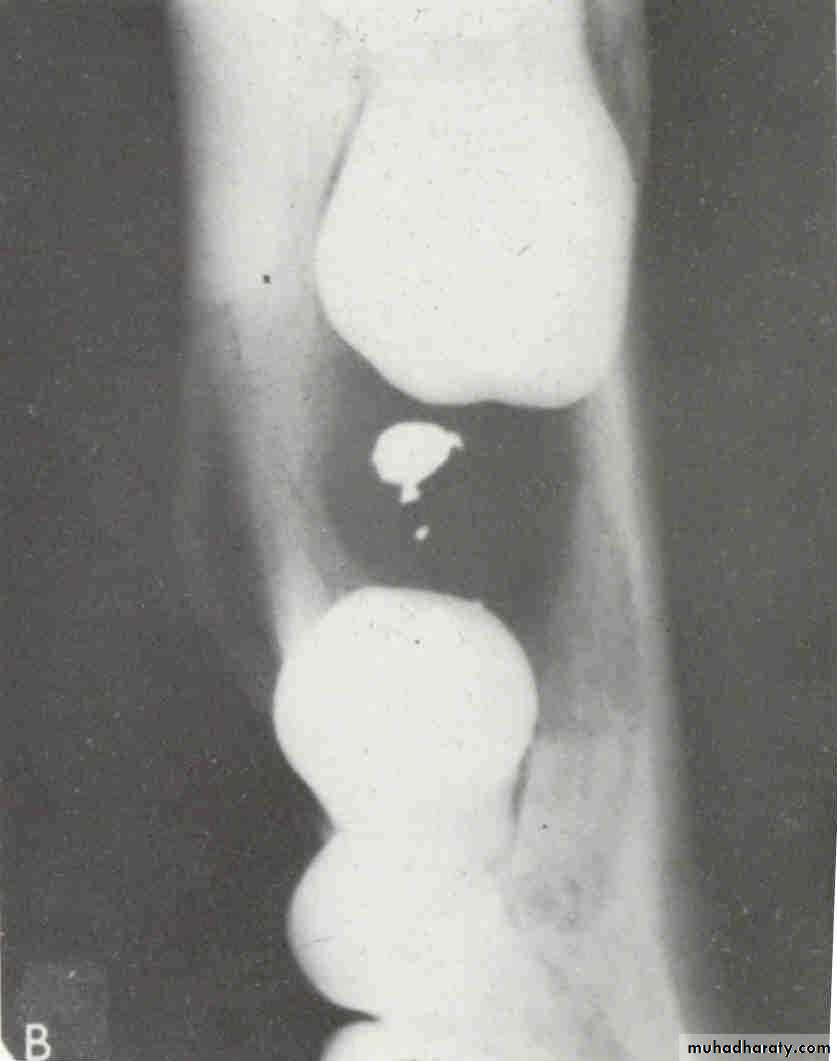

premolar filmThe arrow in the canine film is pointing to the gutta percha in which canal of the maxillary first premolar?

2

The arrow identifies the lingual canal. The tube head moves mesially from the premolar film to the canine film (beam directed more distally) and the gutta percha indicated by the arrow also moves mesially. (See following slide).